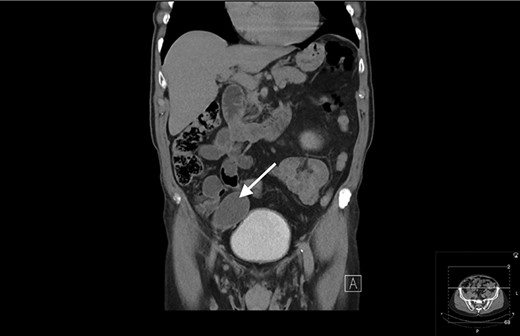

An 80-year-old gentleman was referred to General Surgery by the Urology department following an incidental finding on a computerized tomography (CT) urogram, performed for investigation of haematuria, which self-resolved. The finding was of a well-circumscribed hypodense mass in the right iliac fossa measuring 5.2 × 4 cm. There was subtle focus of calcification at its wall with no communication with the urinary bladder (Figs 1 and 2).

Transverse view of CT showing a well-circumscribed hypodense mass in the right iliac fossa.